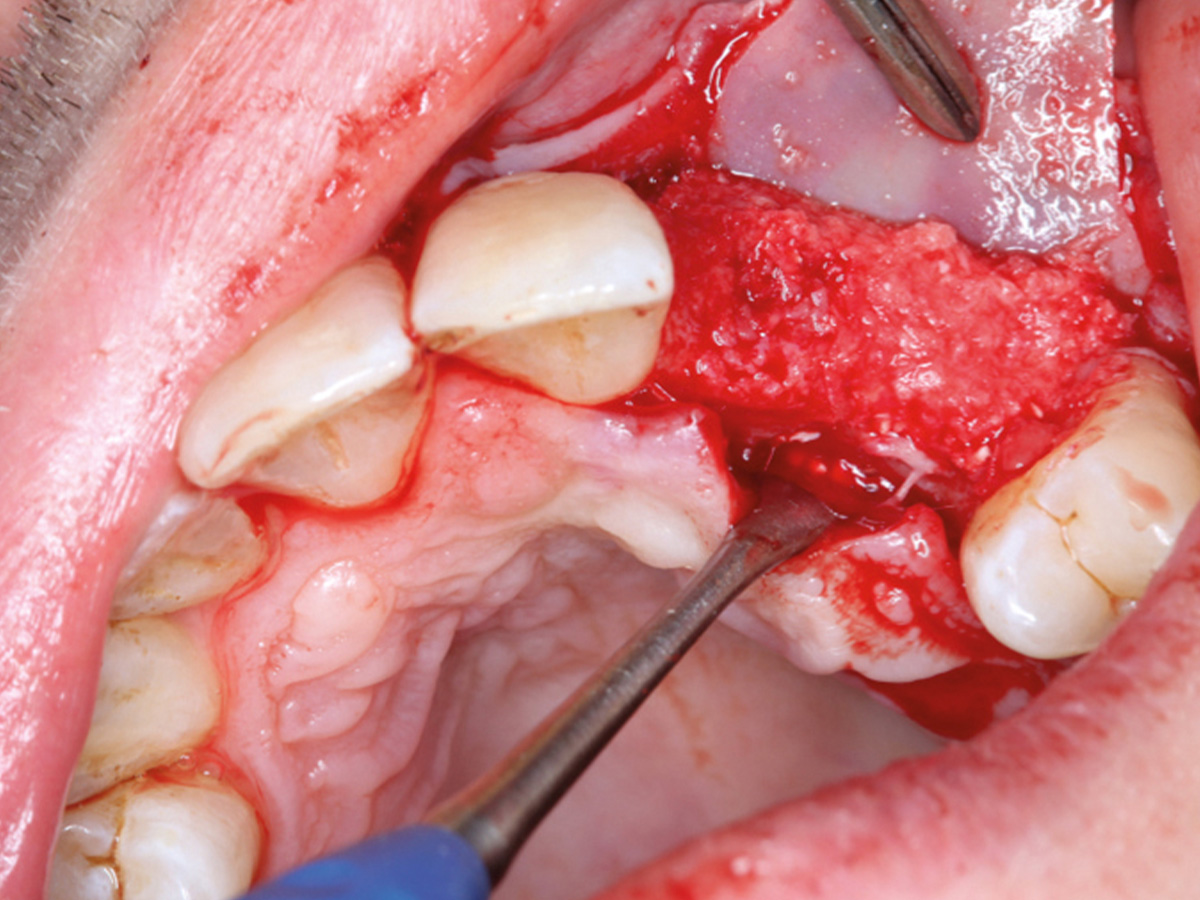

Abbildung 9

Retromolarer Eigenknochengewinn.